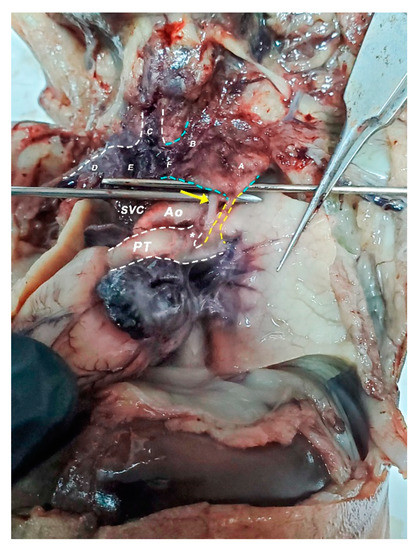

2.2. Dissection